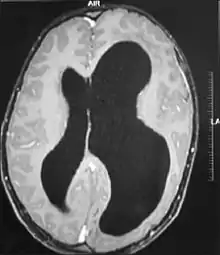

A neurological exam will then be performed using the technology of an MRI machine in order to confirm the diagnosis of megalencephaly. These imaging tests give detailed information regarding brain size, volume asymmetry and other irregular developments linked with MCAP, MPPH and hemimegalencephaly.[2][21]